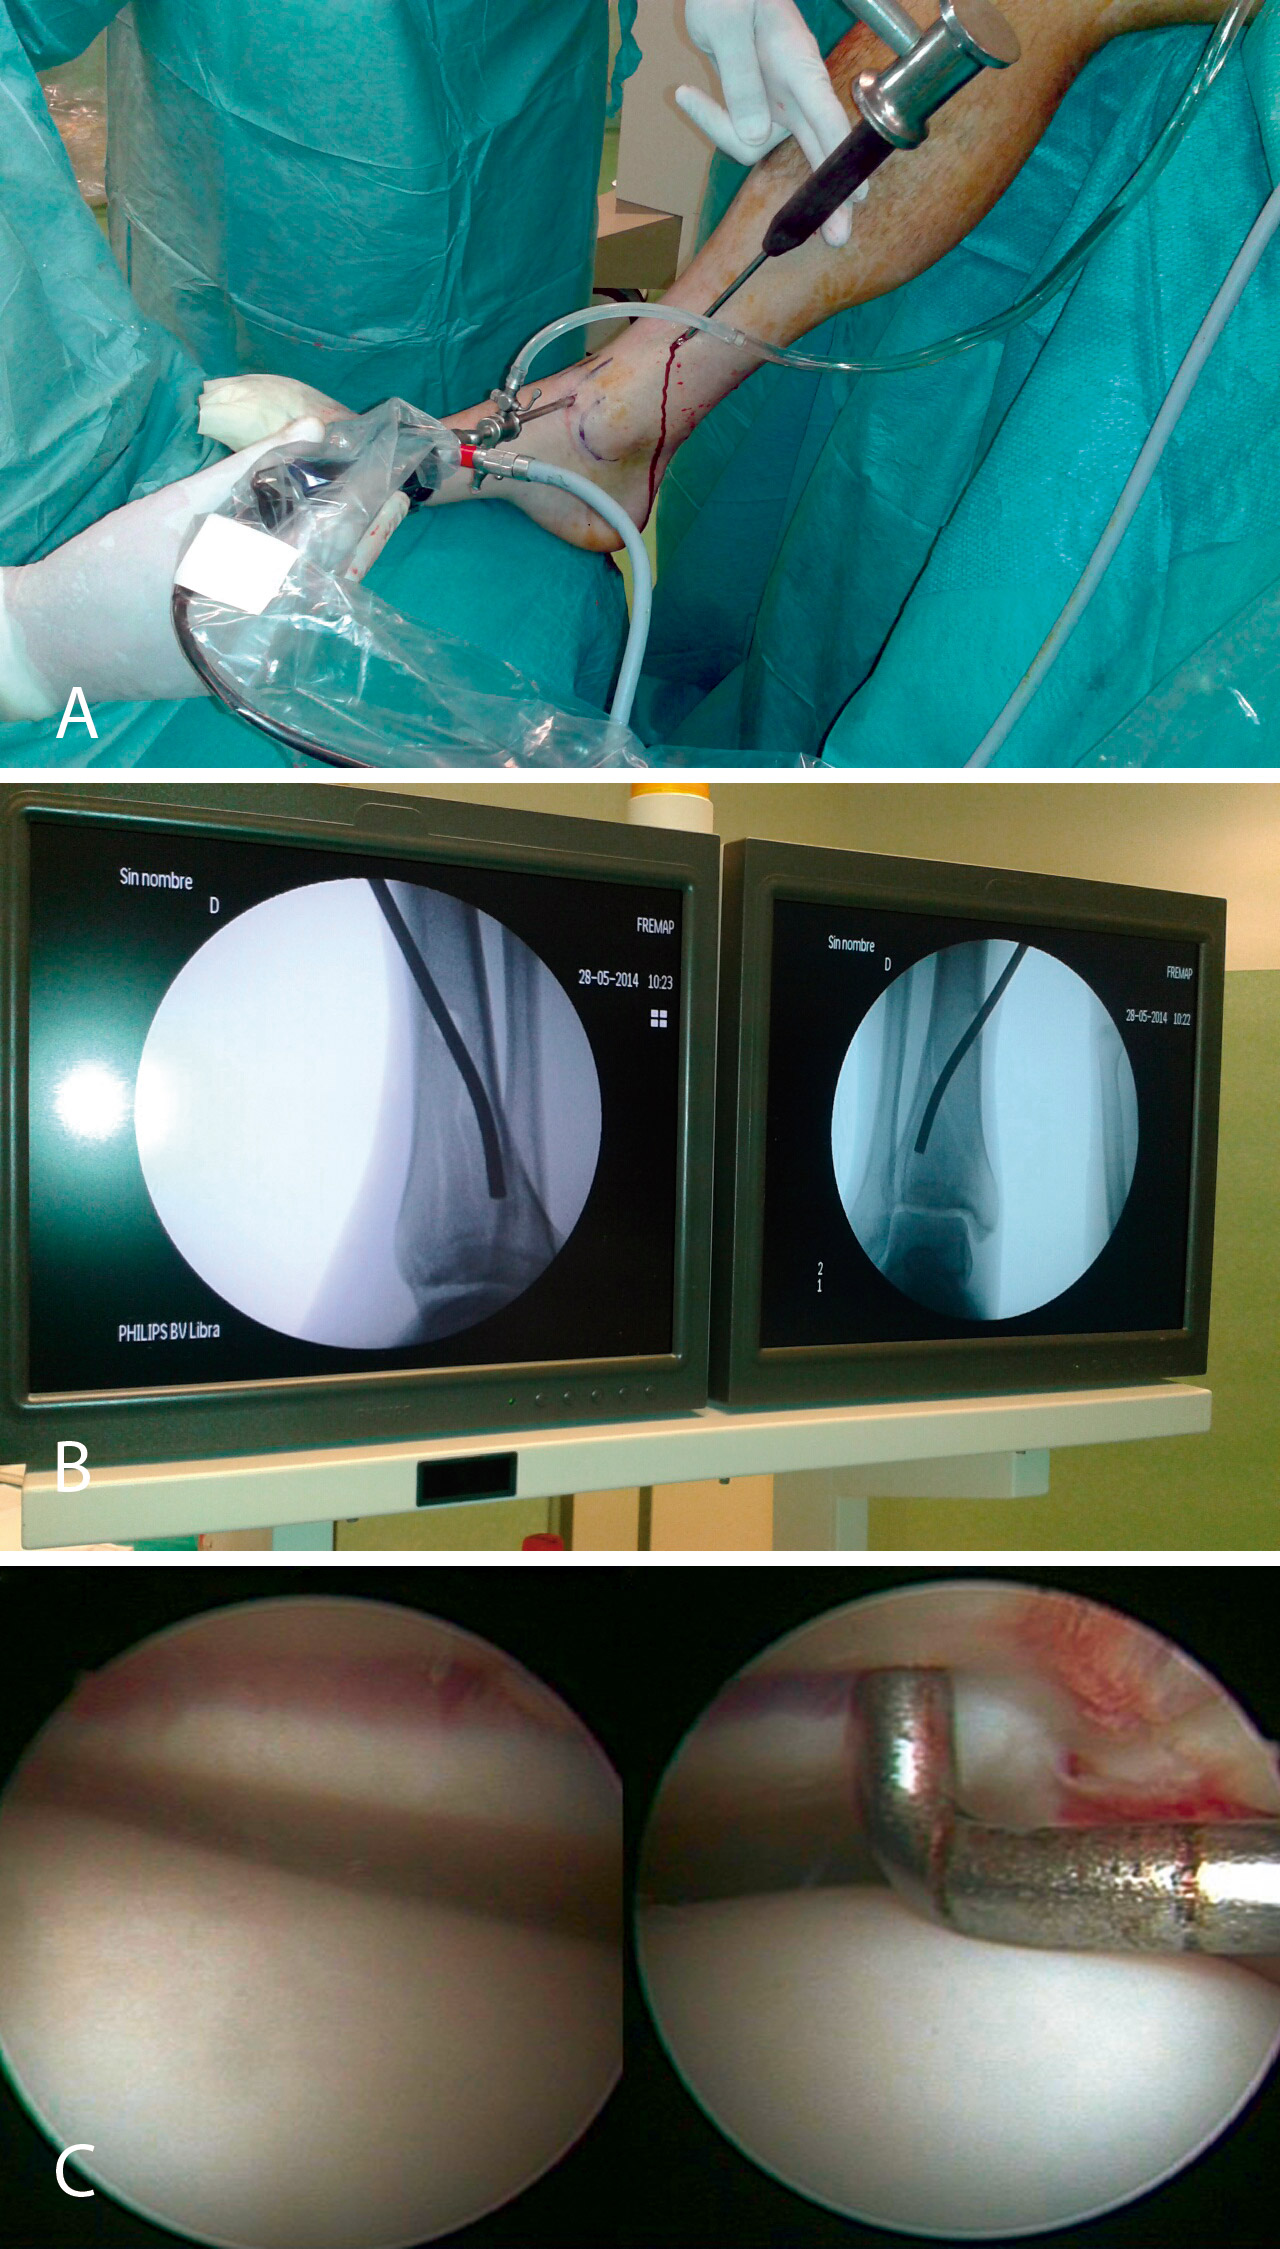

Nos colocamos sentados frente al miembro lesionado, elevando la mesa quirúrgica con la pantalla de la torre de artroscopia frente a nosotros. Tras realizar los portales de artroscopia, procedemos a un lavado exhaustivo de la articulación dejando introducir el suero de la bolsa de artroscopia (no utilizamos bomba de presión) hasta que dejen de salir restos de hematoma por el aspirador de artroscopia. A continuación, introducimos el sinoviotomo y resecamos el hemartros fracturario hasta que identifiquemos los fragmentos del foco de fractura (Figuras 4 y 5).

Figura 4. Caso 1: fractura tipo B2 (fractura-depresión o split fracture). Posición del cirujano y del paciente; colocación del monitor de radioscopia y de artroscopia.

Figura 5. Lavado exhaustivo. Desbridamiento del hemartros y limpieza articular.

Posteriormente, realizamos un orificio en la cortical de la diáfisis de la tibia a cierta distancia del foco de fractura mediante una broca canulada de 8 mm que nos permita introducir un impactor curvo con el que percutir en el fragmento hundido hasta colocarlo a nivel de la superficie articular, controlando la reducción por artroscopia y radioscopia de manera simultánea.

Una vez reducida la fractura, fijamos los fragmentos de manera provisional con una o más agujas de Kirschner y las vamos sustituyendo por tornillos canulados de 4,5 mm. Cuando realizamos este procedimiento, ampliamos habitualmente un centímetro la herida de introducción del tornillo para poder colocar un pequeño separador que nos permita rechazar los elementos neurovasculares y tendinosos de la zona del tobillo.

En cuanto al postoperatorio, inmovilizamos al paciente con una férula de yeso hasta las 3 semanas. A partir de ese momento, colocamos una férula de material termoplástico que se puede retirar para movilizar el tobillo, iniciando la carga con una bota ortésica de tipo Walker a las 6-8 semanas (Figuras 6 a 11).

Figura 6. Realización del orificio en la cortical de la diáfisis con la broca.

Figura 7. Introducción del impactor.

Figura 8. Percusión del fragmento con el impactor, control radioscópico de la posición del impactor e imagen artroscópica del escalón articular antes de la reducción.

Figura 9. Imagen artroscópica de la reducción del fragmento hundido y del trazo articular.